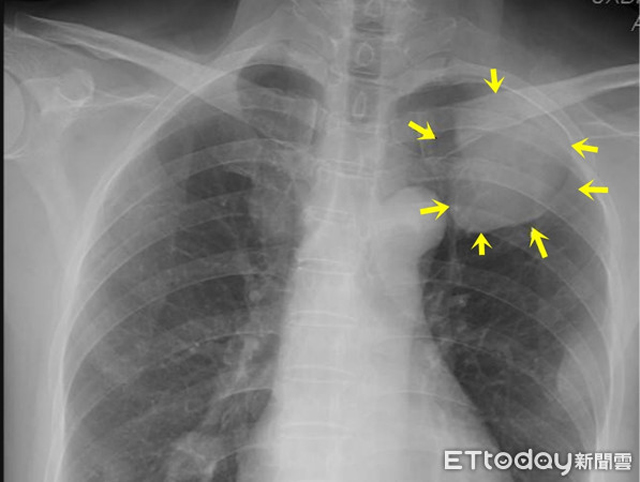

Bác sĩ Lâm Vĩ cho biết: "Kết quả chụp CT cho thấy tế bào ung thư phổi di căn đến thùy đỉnh của não gây ra hiện tượng co giật ở vai phải. Bệnh nhân được chẩn đoán ung thư phổi giai đoạn cuối, các tế bào ung thư phổi đã di căn toàn bộ cơ thể".

Bệnh nhân mắc bệnh ung thư phổi giai đoạn đầu không có triệu chứng rõ ràng, một khi đã có triệu chứng thường được chẩn đoán giai đoạn cuối. Chụp X-quang phổi là một trong những hạng mục khám sức khỏe cơ bản để phát hiện bệnh ung thư phổi, tuy nhiên những tổn thương do ung thư phổi gây ra nhỏ hơn 1cm rất khó phát hiện. Do đó, chụp cắt lớp vi tính lồng ngực liều thấp được coi là phương pháp dễ dàng nhất để phát hiện các tổn thương ung thư phổi giai đoạn đầu.